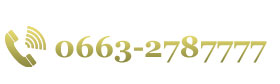

康美醫院開展經皮肺細針穿刺活檢術 ——診斷周圍型肺癌的金标準

發布時間:2018-01-22 閱讀:4137 患者劉某,女,62歲,因“發現頸部淋巴結腫大2月餘”于本月6日入院。檢查雙側頸部可扪及多個大小約1*0.5cm淋巴結,質硬,無壓痛。入院後經胸部CT增強平掃發現右肺上葉腫塊,結合腫瘤标志物檢測,考慮肺癌。

由于周圍型肺癌分型不同,治療方案不同。以往醫學界隻能在患者術後取腫瘤組織送病理檢查,才能确診其良惡性以及對腫瘤分型,即是先手術後确診。而經皮肺穿刺活檢術把診斷提到了前面,即先确診後治療,對周圍型肺腫瘤的診療無疑有重大意義。

由于周圍型肺癌分型不同,治療方案不同。以往醫學界隻能在患者術後取腫瘤組織送病理檢查,才能确診其良惡性以及對腫瘤分型,即是先手術後确診。而經皮肺穿刺活檢術把診斷提到了前面,即先确診後治療,對周圍型肺腫瘤的診療無疑有重大意義。